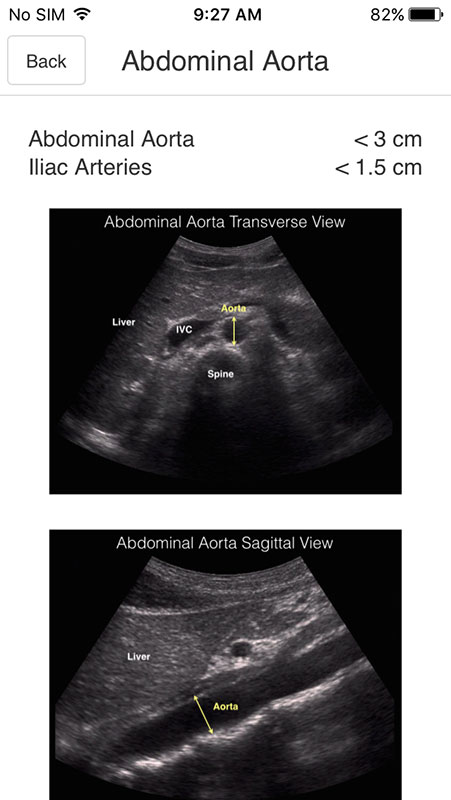

Selecting the subcategory opens a screen with an ultrasound image of the specific organ. Images are labeled, pointing out specific structures in normal anatomy. Some of the subcategories also contain normal expected values for particular organs. There are also abnormalities in some of the categories tho, but they do not contain ultrasound images, only textual description of pathology values (for example in Ovaries category where Ovarian torsion is explained besides normal image).

For those categories that have an image, there's only one image that features just one view, which, in my opinion, isn't sufficient to show normal ultrasound anatomy. There should be multiple images from different angles, and perhaps even comparisons to an illustrated images depicting the organ.

To see the image in more detail, you just need to tap on it, which expands the image (zooms in). However, this part isn't implemented so well. The image expands outside the screen and there's no option to fit it inside. The horizontal rotation doesn't work, so users are stuck with a vertical view, which isn't mobile friendly.

Also, the app creators claim that images are high quality, but in reality, they're not. They stay the same resolution when you expand them, only looking a bit grainier. I expected this part to be much better in the app that focuses on ultrasound imaging.